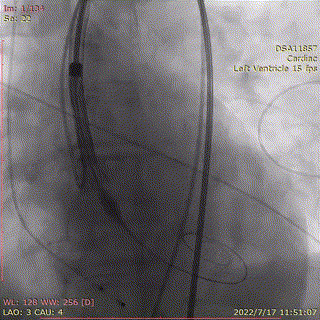

输送系统顺滑缓慢过弓,跨瓣,AV26瓣膜瓣环下0mm定位释放。

输送器跨瓣到位

第一次定位

0位缓慢释放

回收后,重新调整到工作位后,造影显示瓣膜位置良好,第2次0位释放,释放脱钩后瓣膜形态、位置良好,冠脉血流灌注正常,微少量瓣周漏,术后跨瓣压差降至0mmHg。

回收,调整位置

第二次0位释放